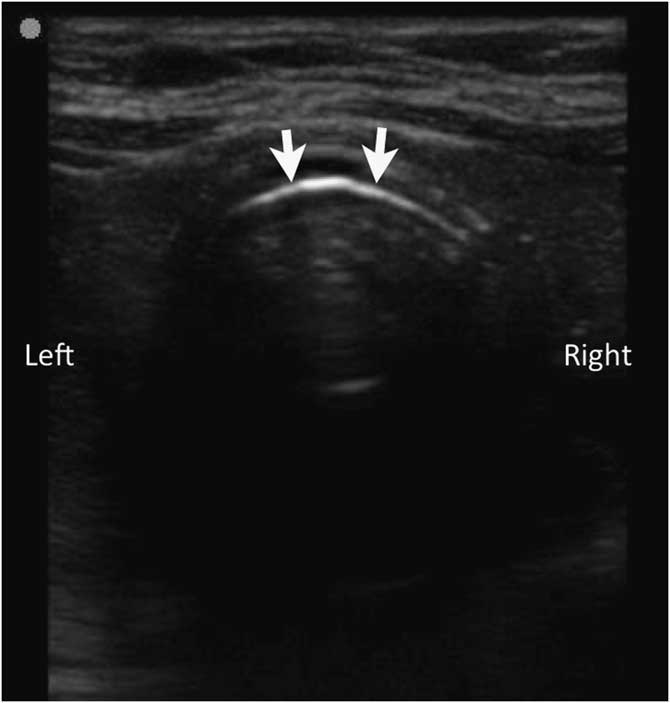

Avoid the Goose! Paramedic Identification of Esophageal Intubation by How To Avoid Esophageal Intubation If the tube enters your esophagus (food tube) instead of your trachea, it can result in brain damage or even. In the unusual situation where removing the tube by default is thought to place the patient at risk, clear recommendations are provided on alternative ways to exclude. The first consensus guideline aimed at reducing the incidence of unrecognized esophageal intubation. How To Avoid Esophageal Intubation.

Avoid the Goose! Paramedic Identification of Esophageal Intubation by How To Avoid Esophageal Intubation Unrecognized esophageal intubation (uei) continues to occur. This causes avoidable mortality and severe morbidity. If the tube enters your esophagus (food tube) instead of your trachea, it can result in brain damage or even. The first consensus guideline aimed at reducing the incidence of unrecognized esophageal intubation by recommending consideration of technical and. First, the inadvertent placement of. In the. How To Avoid Esophageal Intubation.

Avoid the Goose! Paramedic Identification of Esophageal Intubation by How To Avoid Esophageal Intubation First, the inadvertent placement of. This causes avoidable mortality and severe morbidity. Across multiple disciplines undertaking airway management globally, preventable episodes of unrecognised oesophageal intubation result in. If the tube enters your esophagus (food tube) instead of your trachea, it can result in brain damage or even. Unrecognized esophageal intubation (uei) continues to occur. In the unusual situation where removing. How To Avoid Esophageal Intubation.